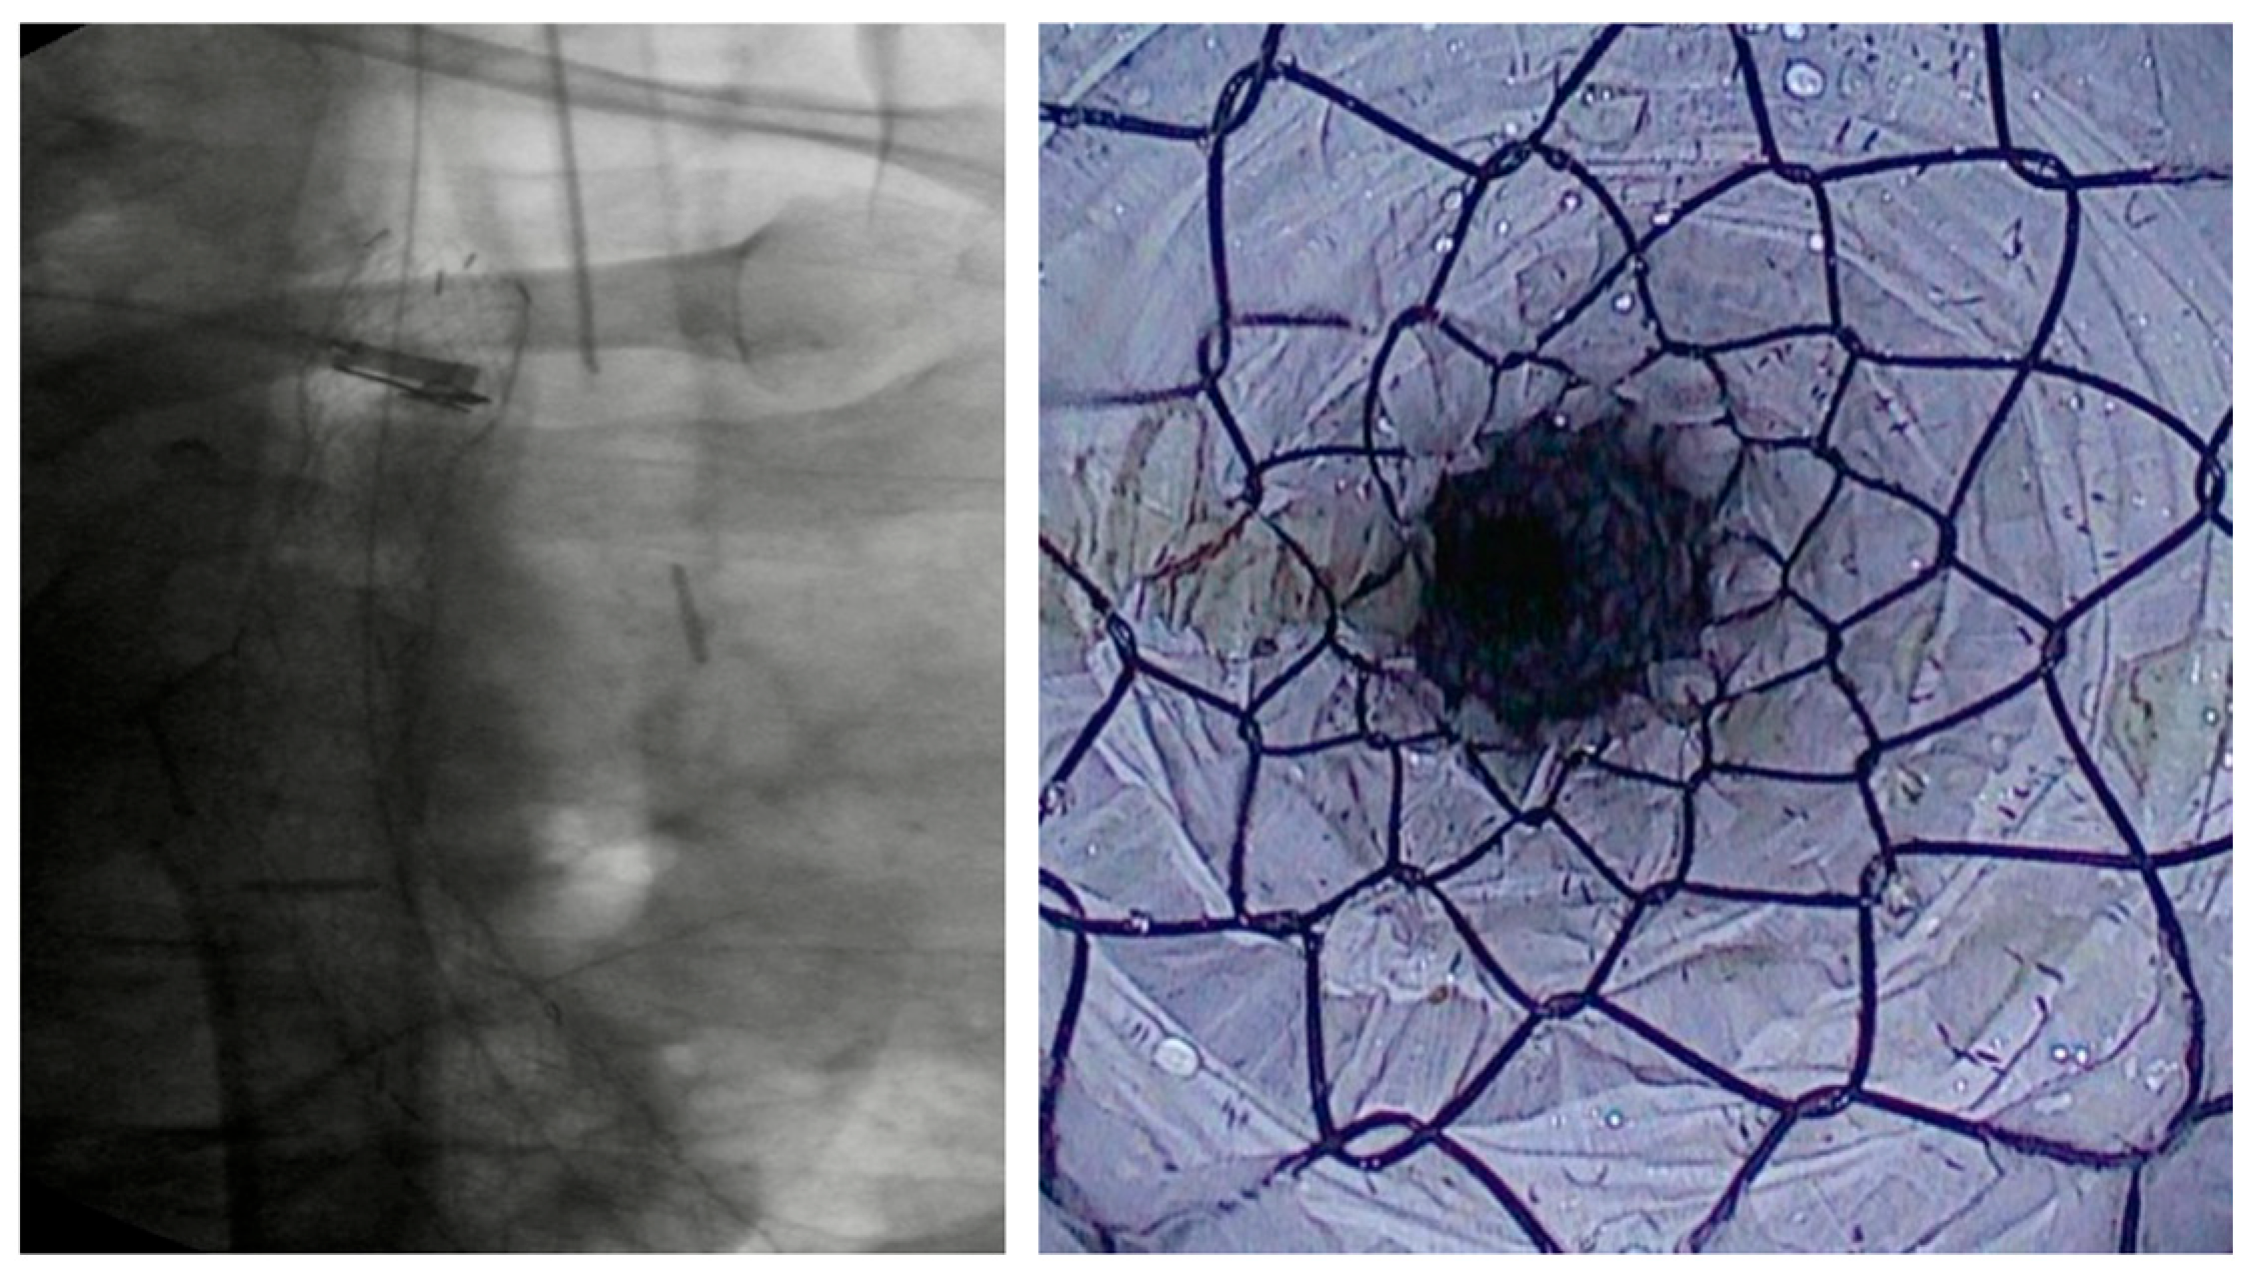

3.1.3. VAC Stent

SEMS vs. VAC Stent